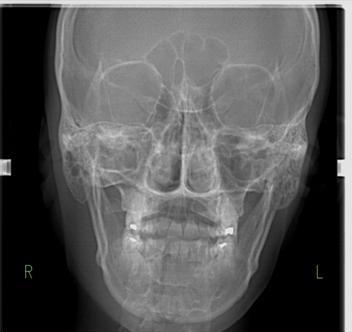

Rx AP

La radiografía anteroposterior es una radiografía útil para diagnosticar fracturas de cóndilos mandibulares y arco zigomático y simetría facial.